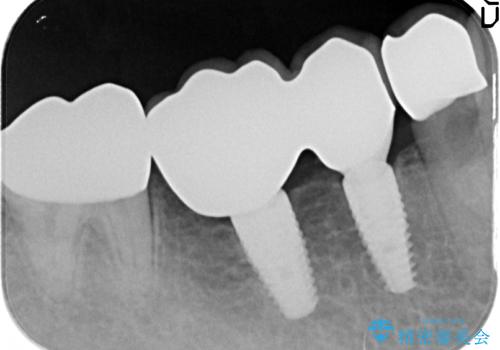

- 80万円(ストローマンインプラント×2・チタンカスタムアバットメント×2・ジルコニアクラウン×4)費用は治療当時の料金となります

インプラントを用いることで残っている歯の負担も減らし、長期的な予後を見込むことができます。